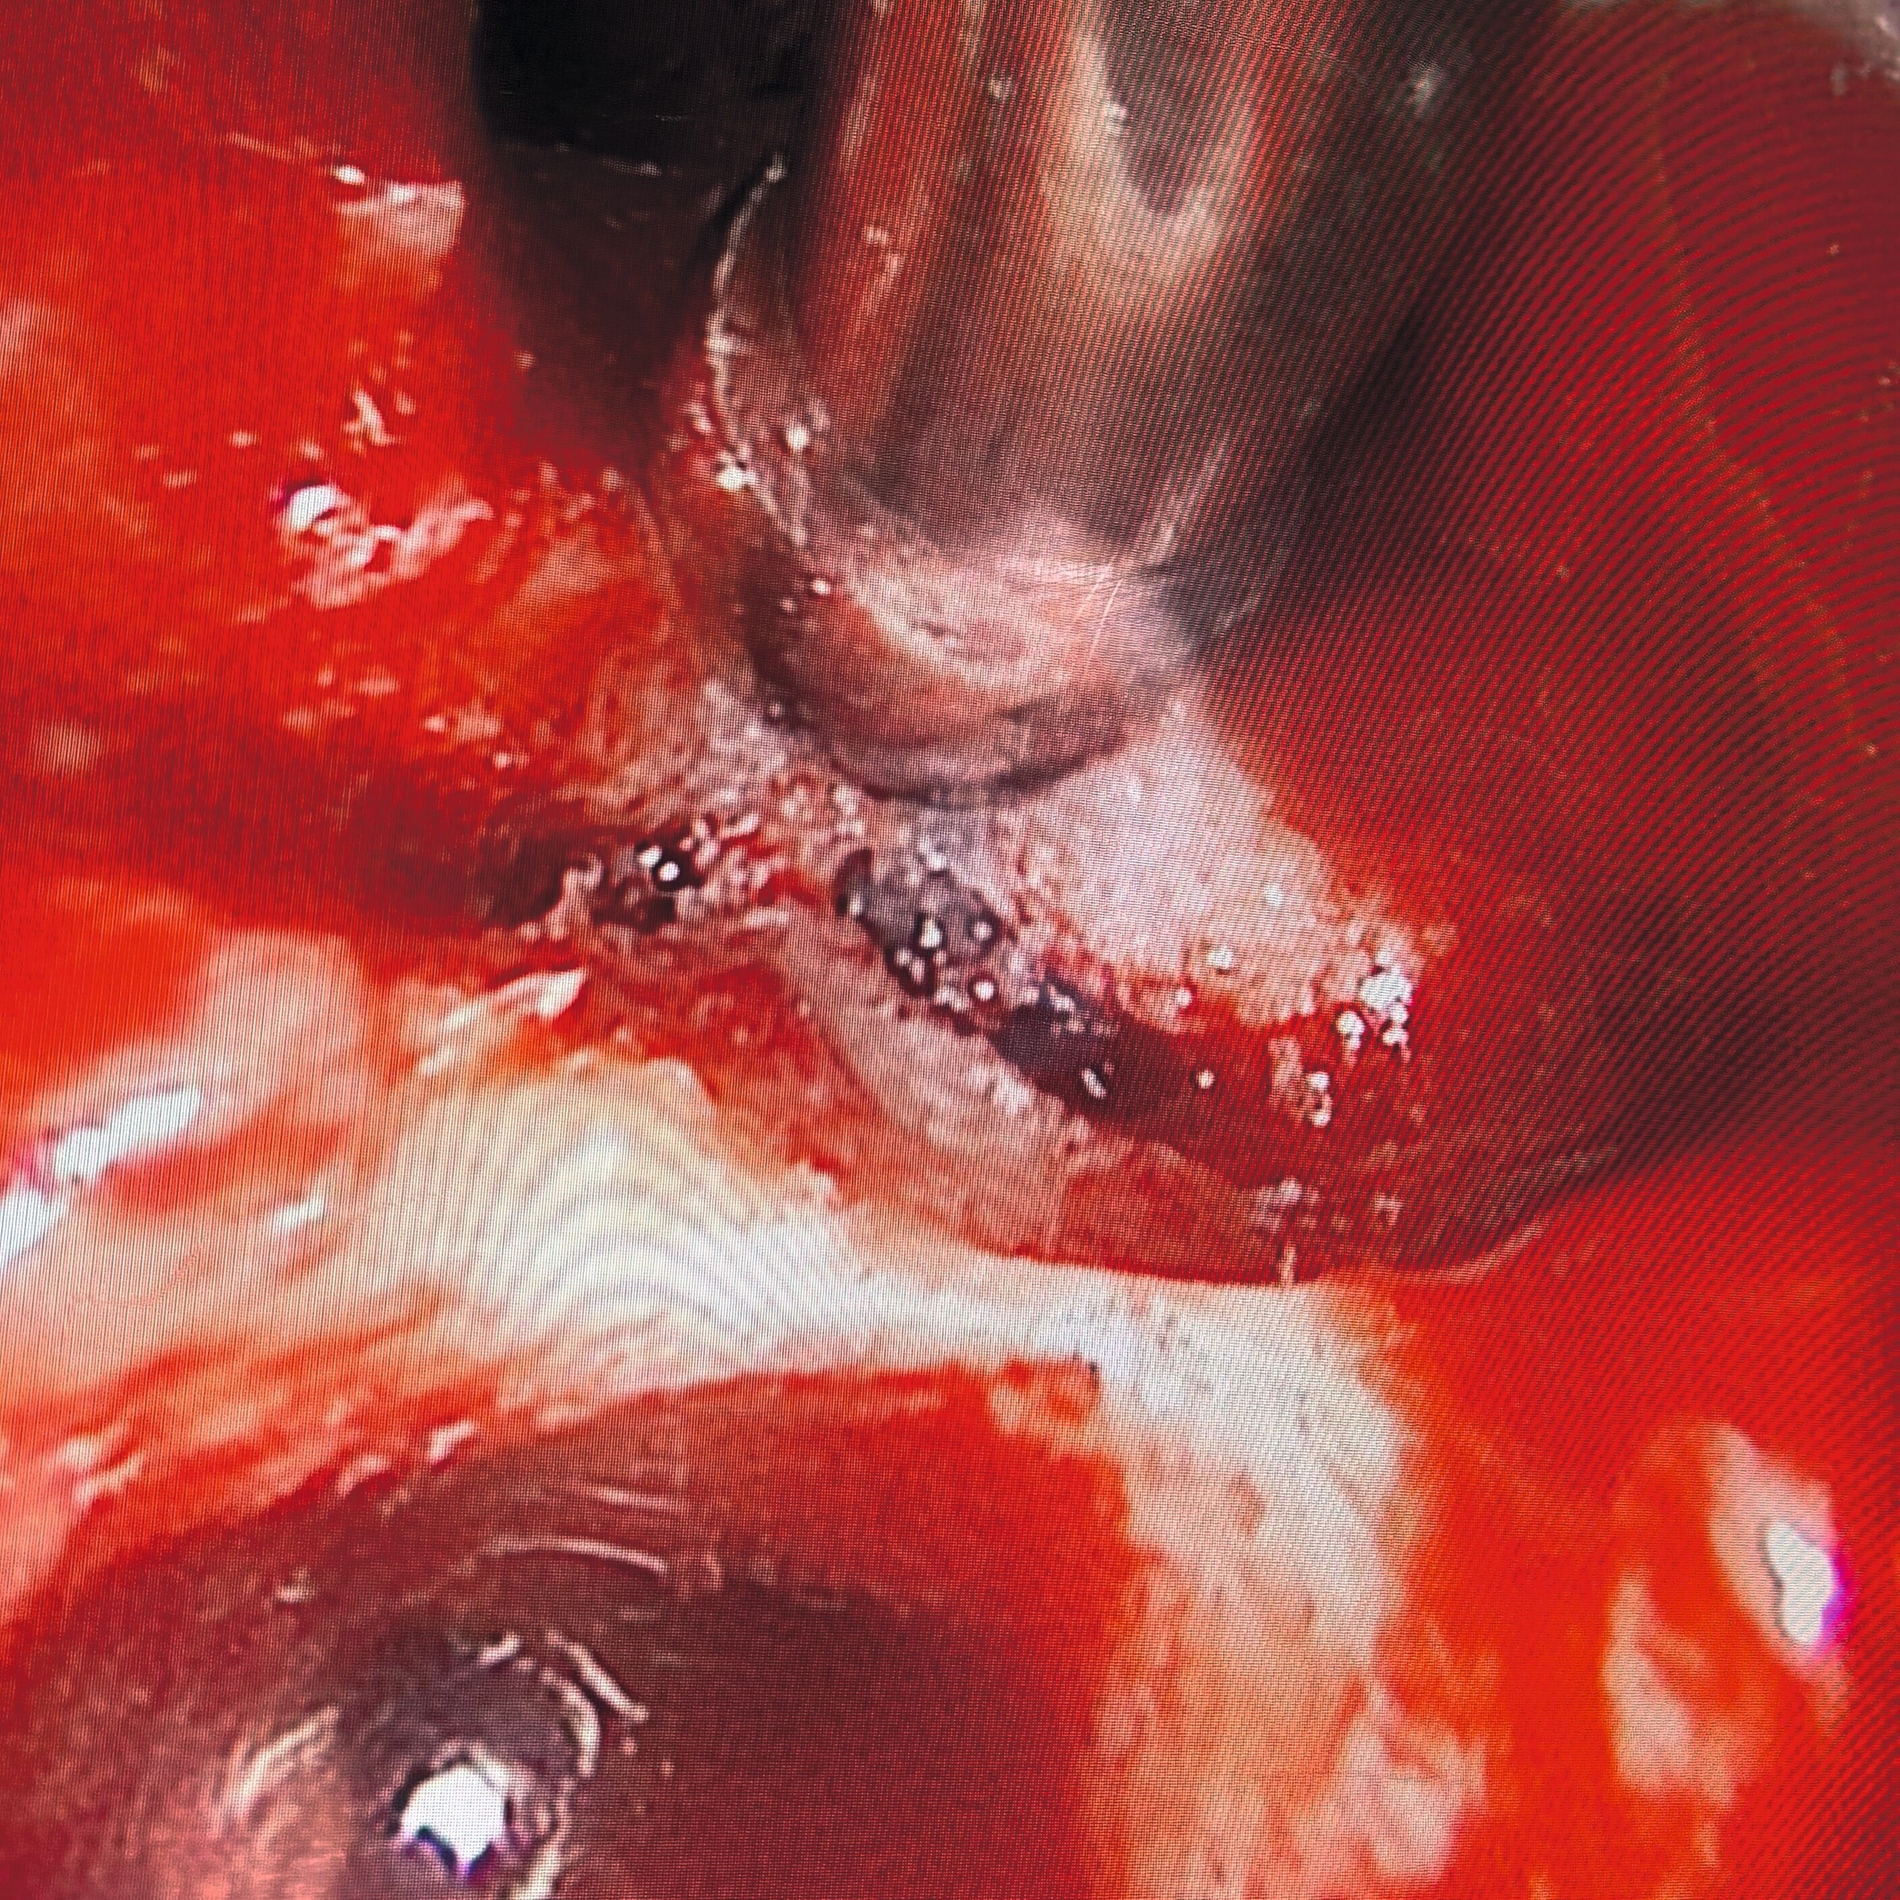

Intraoperativ zeigte sich die interradikuläre Perforation im Sinne eines Fistelgangs zur linken Kieferhöhle (Abb. 8), die bereits präoperativ in der alio loco durchgeführten MRT-Bildgebung erkennbar gewesen war (Abb. 7). Zudem entfernten wir das Empyem und die pathologisch veränderte Schleimhaut sowie das Narbengewebe unter Schonung der noch intakten Schneider’schen Membran.